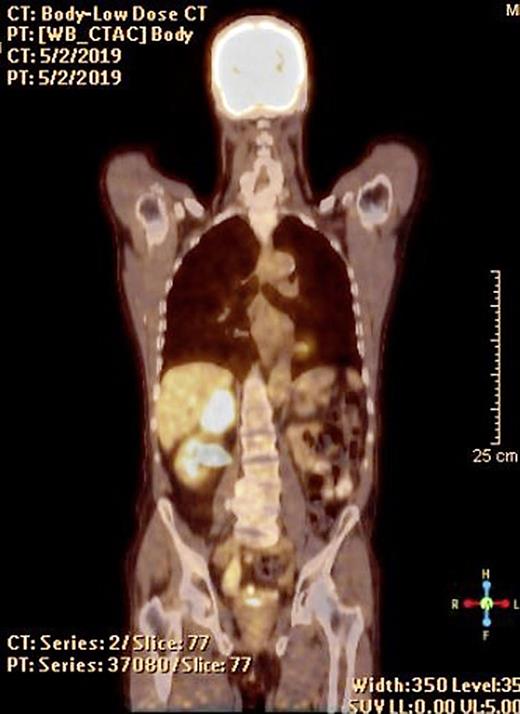

Metabolic Steal of the Myocardium by Primary Cardiac Lymphoma Case Case Reports In Oncology Karger Regarding positive outcomes, there is one prospective trial with 4 pr and 2 case reports and our case showing good responses to. Added 14 december 2009 • updated 4 april 2024. Oncology | case reports in oncology | karger publishers. Goblet cell adenocarcinoma (gca) of the appendix is an uncommon type of cancer that includes both. Two case reports of. Case Reports In Oncology Karger.